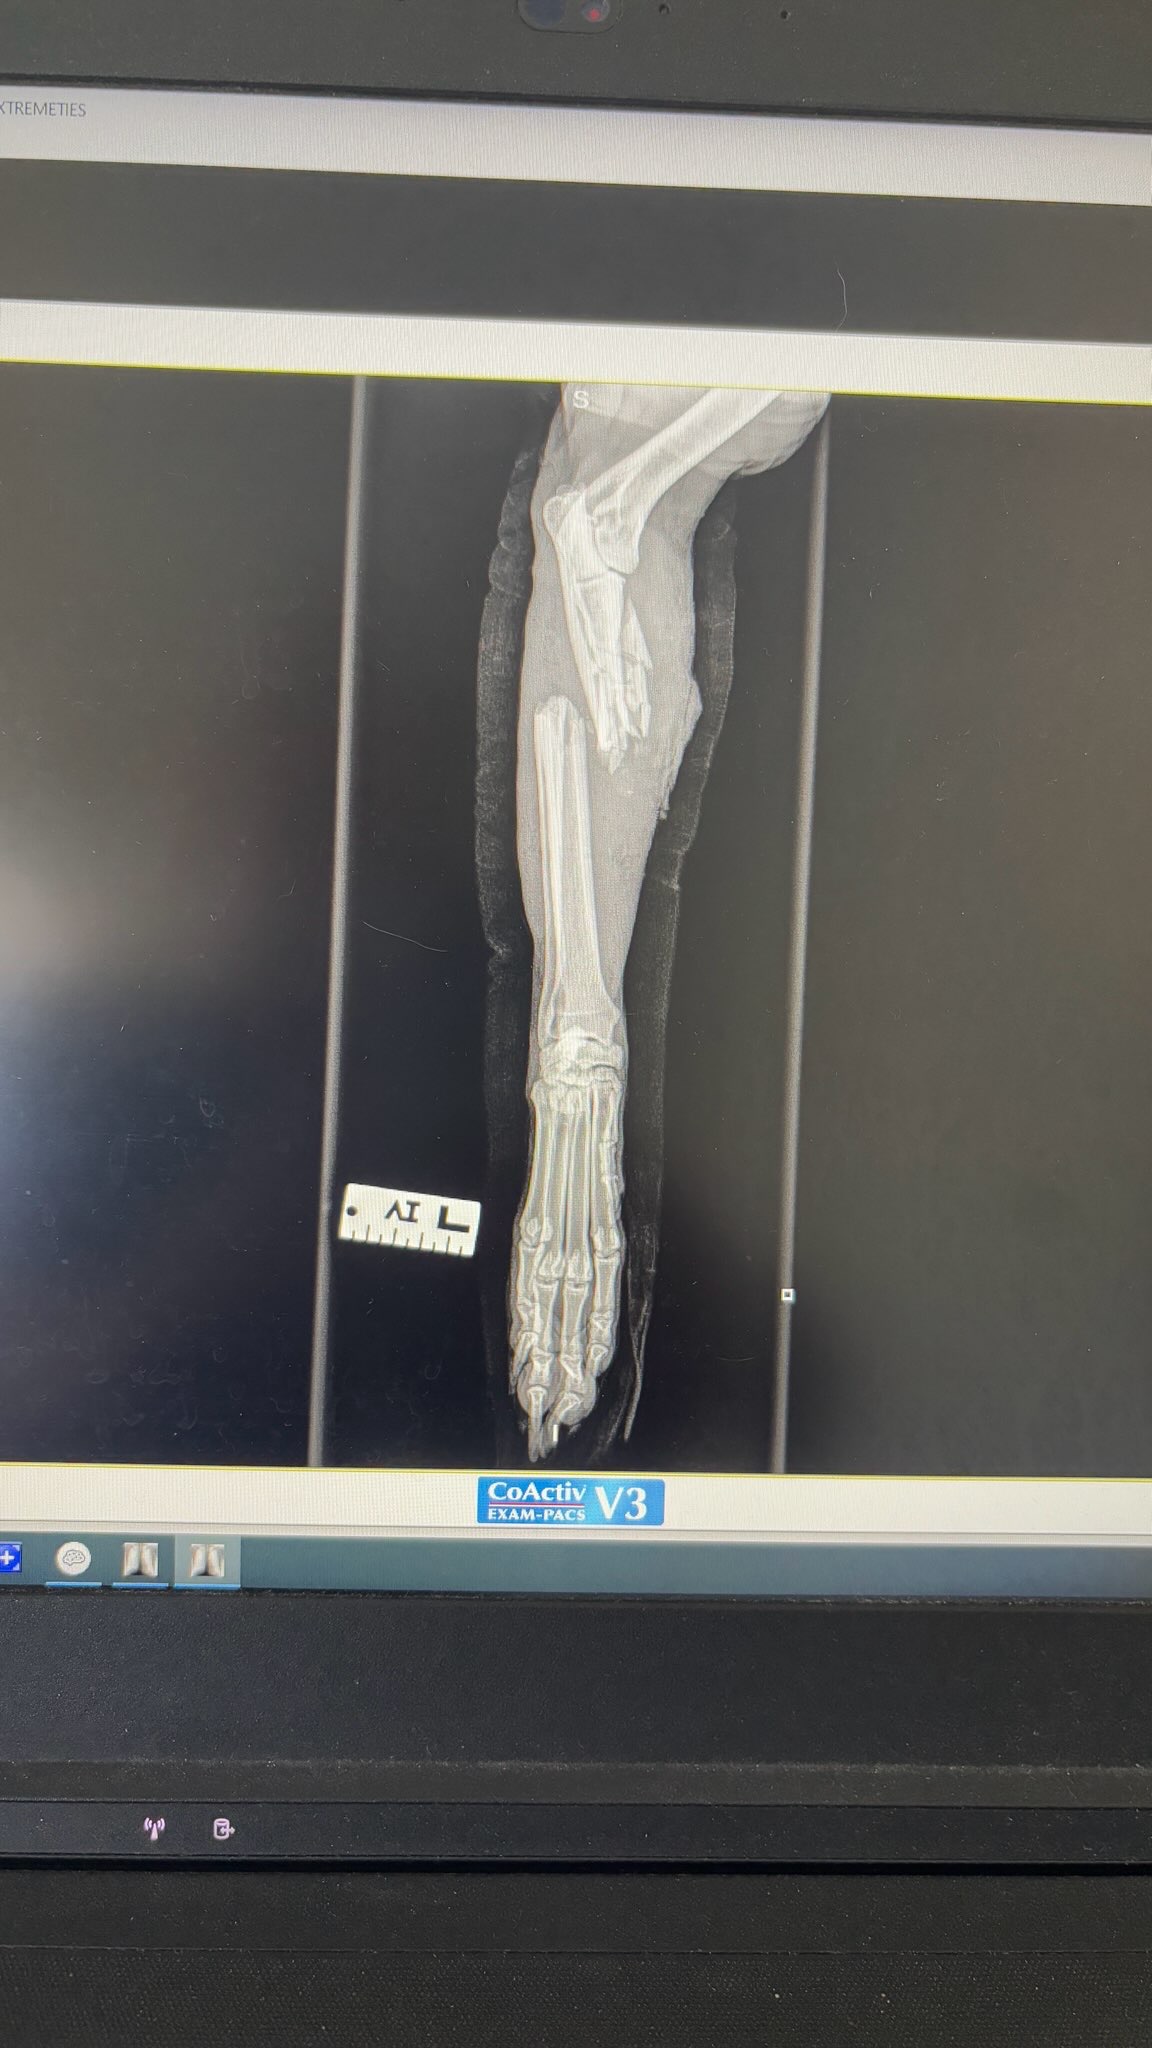

I wanted to share something tough that happened yesterday. My dog Max was hit by a car on Hope Street. Thankfully, he survived, but he suffered a serious injury — a fracture in his left leg that unfortunately can’t be repaired. After speaking with the vets, the best option for him now is to amputate the leg so he can heal and live without constant pain.